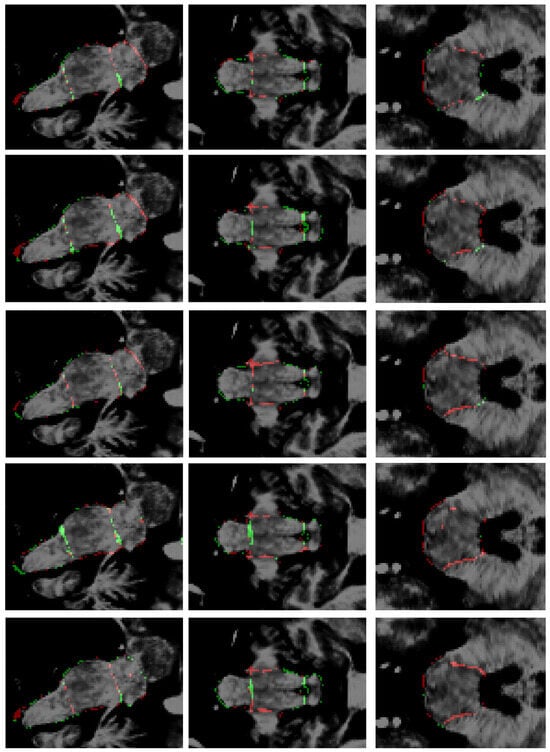

| Label | Mean DSC ± stdev | ||||

|---|---|---|---|---|---|

| This Research | Cabeza-Ruiz et al. [54] | Han et al. [38] (Modified) | Magnusson et al. [69] | Nishimaki et al. [40] (Modified) | |

| Mesencephalon | 0.96 ± 0.022 | 0.92 ± 0.019 | 0.93 ± 0.019 | 0.89 ± 0.031 | 0.91 ± 0.022 |

| Pons | 0.96 ± 0.015 | 0.94 ± 0.014 | 0.94 ± 0.013 | 0.91 ± 0.029 | 0.93 ± 0.014 |

| Medulla | 0.95 ± 0.021 | 0.93 ± 0.020 | 0.92 ± 0.021 | 0.91 ± 0.023 | 0.93 ± 0.021 |

| Full brainstem | 0.96 ± 0.008 | 0.95 ± 0.008 | 0.95 ± 0.007 | 0.93 ± 0.013 | 0.95 ± 0.007 |

| Measures | Score (Mean Value) | ||||

| IoU | 0.914 ± 0.01 | 0.904 ± 0.01 | 0.906 ± 0.01 | 0.886 ± 0.05 | 0.906 ± 0.01 |

| HD95 (mm) | 2.71 | 3.02 | 2.78 | 3.29 | 2.65 |

| Specificity | 0.998 ± 0.0007 | 0.998 ± 0.0007 | 0.998 ± 0.0006 | 0.997 ± 0.001 | 0.998 ± 0.0007 |

| Sensitivity | 0.949 ± 0.01 | 0.938 ± 0.02 | 0.941 ± 0.02 | 0.928 ± 0.05 | 0.947 ± 0.01 |

| Precision | 0.972 ± 0.01 | 0.963 ± 0.01 | 0.950 ± 0.01 | 0.939 ± 0.01 | 0.953 ± 0.01 |

| ASD | 0.052 | 0.058 | 0.058 | 0.079 | 0.054 |

| NSD | 0.993 | 0.991 | 0.992 | 0.985 | 0.992 |